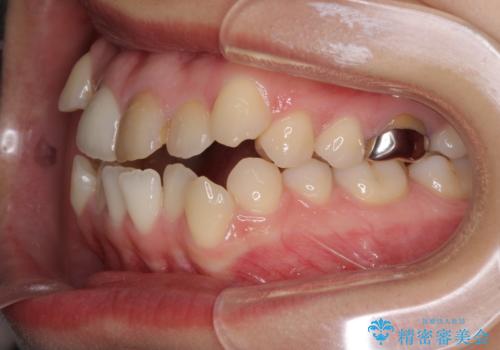

- 上の八重歯を気にして来院された患者様です。

受け口傾向にあるため、上顎前歯の叢生解消とともに下顎前歯を後方へ移動させることを目的とし、上下左右の第一小臼歯4歯を抜歯することとしました。

受け口傾向の方の下顎抜歯矯正では、下顎前歯の歯肉が退縮することがあります。前歯を移動させるときには、歯肉退縮が起こらないように工夫する必要があります。